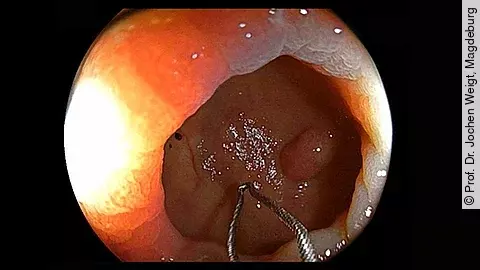

Endoskopisches LehrvideoAPC und Clip bei blutender Angiodysplasie im Magen

In unserem neuen Endoskopie-Video erfahren Sie, wie eine blutende Angiodysplasie im Magen aus einer Kombination mit Argon-Plasma-Koagulation (APC) und Clip behandelt werden kann. Dabei zeigt Ihnen PD Dr. Jochen Weigt vom Uniklinikum Magdeburg, was bei der Durchführung empfehlenswert ist.